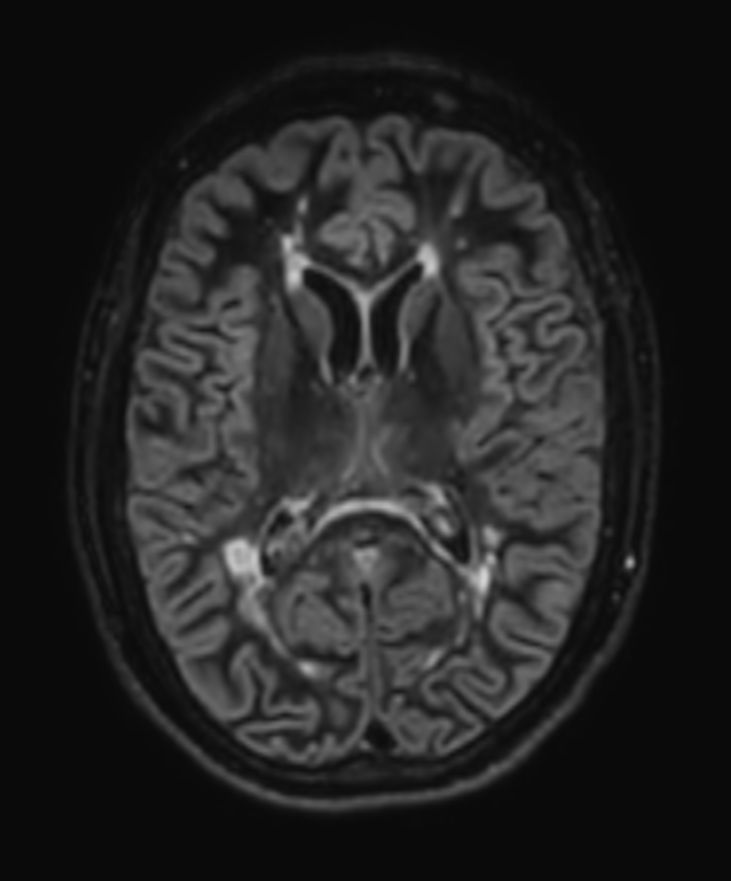

3D T2w FLAIR BrainVIEW Compressed SENSE